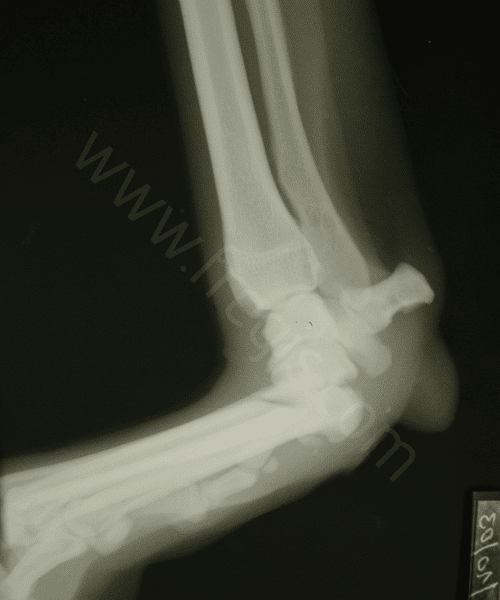

Radiographie de l’extrémité de la patte arrière d’un chien présenté pour palmigradie traumatique. L’articulation du carpe fait ici un angle droit tout à fait anormal.